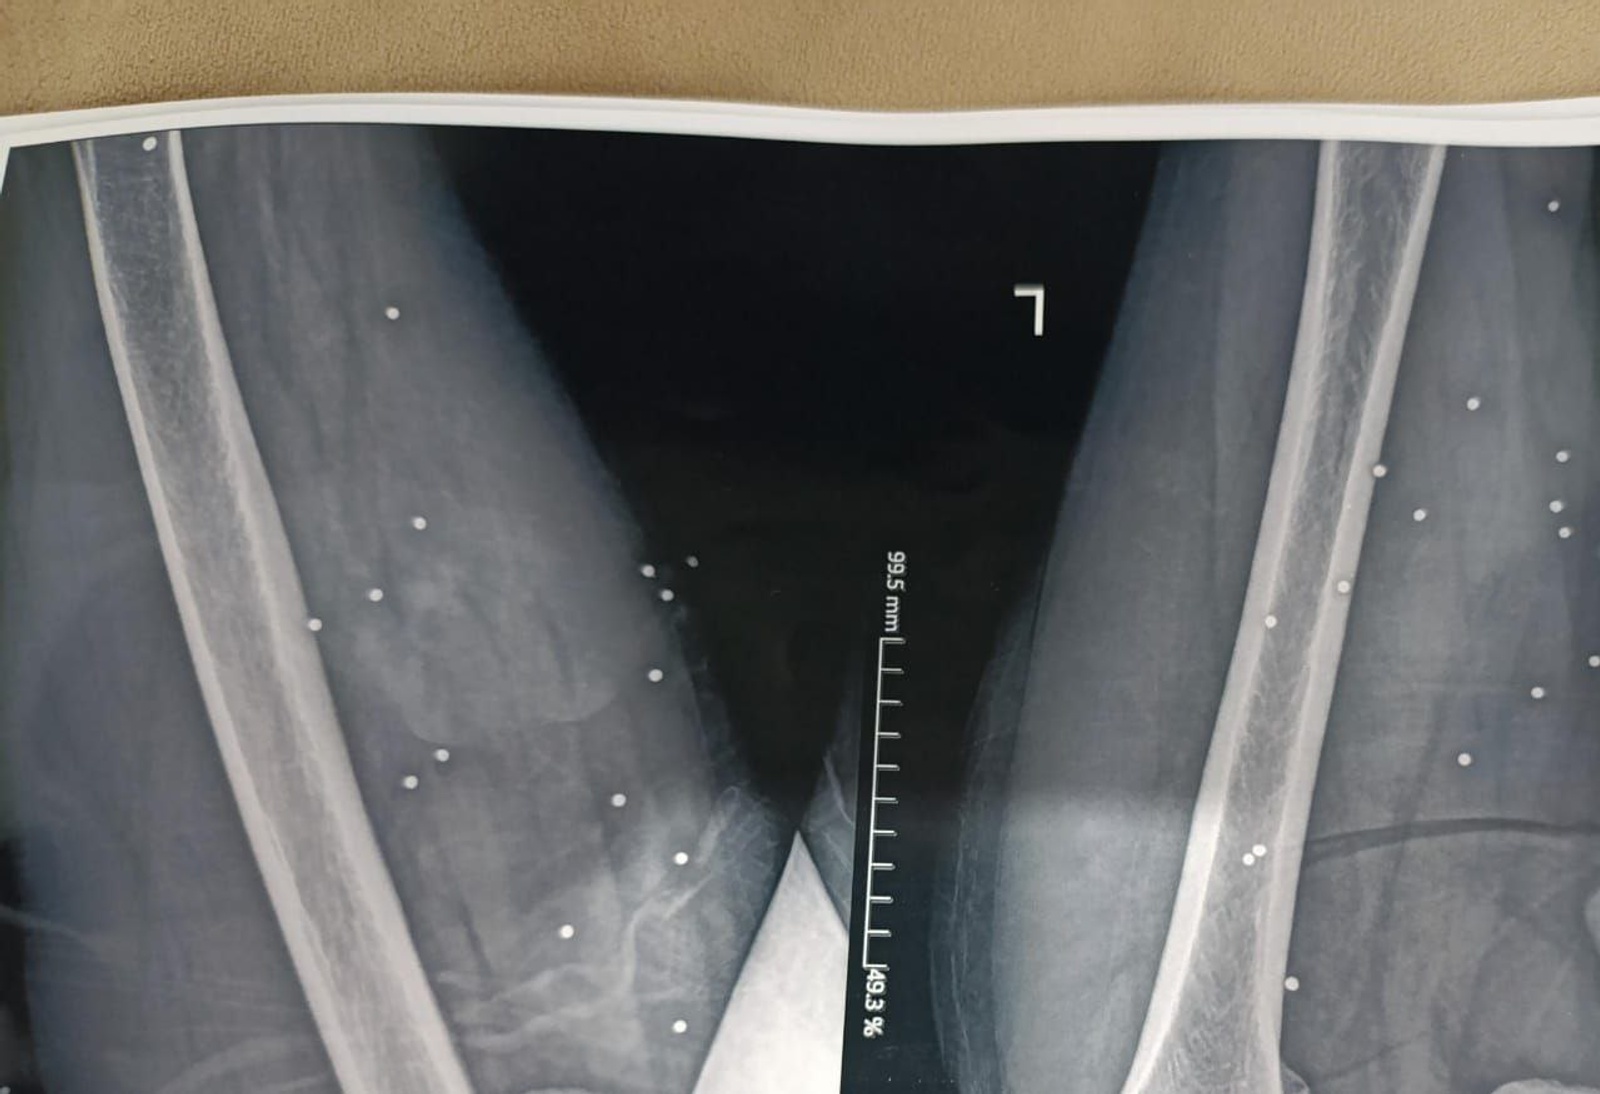

به گزارش روزنامه گاردین، بررسی ده‌ها تصویر پزشکی ثبت‌شده در جریان سرکوب اعتراضات در ایران نشان می‌دهد معترضان با ساچمه‌های فلزی و گلوله‌های کالیبر بالا هدف قرار گرفته‌اند. تصاویری که به گفته کارشناسان، از شدت جراحات و الگوی اصابت به نواحی حیاتی بدن حکایت دارند.

تصویر او یکی از بیش از ۷۵ مجموعه تصویر پزشکی شامل رادیولوژی و سی‌تی‌اسکن است که از یک بیمارستان در یکی از شهرهای بزرگ ایران به دست آمده و در اختیار گاردین قرار گرفته است. تصاویری که در طول یک شب و هم‌زمان با سرکوب اعتراضات دی‌ماه ثبت شده‌اند.

تصاویر، روایتی از شدت خشونت علیه معترضان و رهگذران ارائه می‌دهند.

ساچمه‌هایی که می‌توانند مرگبار باشند

ایران از معدود کشورهایی است که نیروهای امنیتی آن از ساچمه فلزی علیه شهروندان و برای سرکوب معترضان استفاده می‌کنند. هرچند هر ساچمه به‌اندازه گلوله جنگی قدرت تخریب ندارد، اما تعداد زیاد آن‌ها می‌تواند آسیب‌هایی بسیار شدید ایجاد کند.

گاردین در گزارش خود تاکید کرد که در برخی تصاویر، تنها یک یا دو ساچمه در جمجمه دیده می‌شود که پس از عبور از چشم در حفره آن متوقف شده‌اند.

در موارد دیگر، صدها ساچمه در بدن پراکنده شده و بافت نرم را تخریب کرده‌اند.

در پرونده «علی»، بیش از ۱۷۴ ساچمه در قفسه سینه راست دیده می‌شود. تراکمی که نشان می‌دهد شلیک از فاصله بسیار نزدیک انجام شده است. ریه راست او آسیب شدید دیده و تجمع خون و هوا در اطراف آن مشاهده می‌شود.

کارشناسان پزشکی گفته‌اند حتی با مداخله فوری، خطر مرگ در چنین شرایطی بالاست.

گلوله‌های تمام‌فلزی

در ۹ بیمار، گلوله‌های کالیبر بالا همچنان در بدن باقی مانده و در تصاویر دیده می‌شوند.

در موارد دیگر، مسیر شکستگی استخوان و قطعات فلزی باقی‌مانده نشان می‌دهد احتمالا اصابت گلوله‌های پرسرعت، عامل جراحت بوده‌اند.

کارشناسان این مهمات را از نوع «تمام‌فلزی» معرفی کرده‌اند؛ گلوله‌هایی که معمولا با سلاح‌هایی مانند ای‌کی-۴۷ (AK-47) شلیک می‌شوند و شکل خود را حفظ می‌کنند.

یکی از کارشناسان به گاردین گفته است: «این‌ها سلاح‌هایی با هدف کشندگی هستند.»